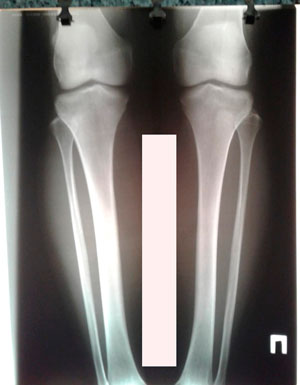

Исходник -43 года.

Дата операции - 18.07.2019г.

Диагноз: нетипичная варусная деформация голеней, на границе нижней и средней/3

Исправление по методике доктора Онипко Н.Н.